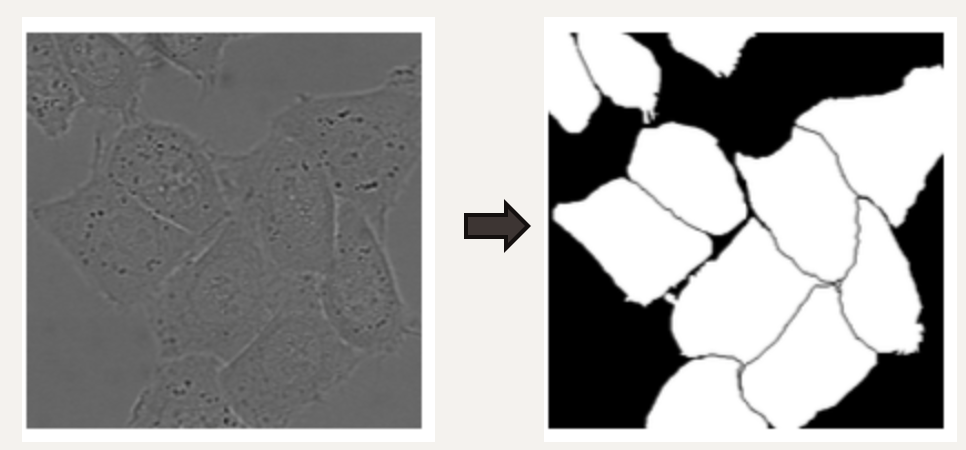

모델은 위 그림처럼 작은 경계를 분리할 수 있도록 학습되어야 합니다. 따라서 논문에서는 각 픽셀이 경계와 얼마나 가까운지에 따른 Weight-Map을 만들고 학습할 때 경계에 가까운 픽셀의 Loss를 Weight-Map에 비례하게 증가 시킴으로써 경계를 잘 학습하도록 설계하였습니다.